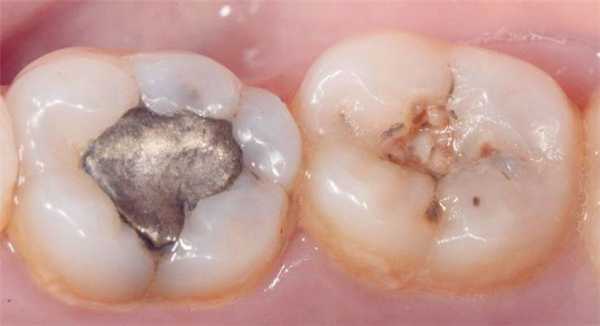

Клинический случай 1

35-летняя пациентка обратилась за стоматологической помощью с просьбой заменить амальгамные реставрации в области первого и второго нижних молярах. Она также сообщала о наличие болезненных ощущений в проекции данных зубов при жевании. В ходе клинического осмотра были идентифицированы реставрации моляров, требующие срочной замены (фото 4). После удаления старых пломб и нанесения универсального адгезива Adhese Universal, объем дентина был восстановлен материалом Tetric EvoFlow Bulk Fill (фото 5). Данный композит обладает очень хорошими свойствами самовыравнивания и автоматически принимает вогнутую форму. В области второго моляра текучий композит вносили одновременно и на окклюзионную и на контактную поверхности. Полимеризацию обеспечивали лампой Bluephase (1200 мВт/см2) в течение 20 секунд. Производитель рекомендует обеспечивать полимеризацию композита на протяжении 10 секунд. Внесенная толщина слоя текучего композита не превышала 4 мм. Благодаря технологии Aessencio опаковость материала значительно увеличивается в процессе полимеризации (фото 5). Эмаль восстанавливали посредством материала Tetric EvoCeram A3, используя технику последовательного наращивания бугров. Фиссуры окрашивали при помощи IPS Empress Direct Color Brown (фото 6). Корректировку окклюзионных соотношений проводили после удаления коффердама. Поскольку бугорки изначально были смоделированы правильно, требовалась лишь минимальная окклюзионная коррекция, после которой приступили к полировке реставрации системой Astropol. Поверхности реставраций плавно сливались с окружающей структурой зуба (фото 7).

Фото 4. Дефектная реставрация в двух нижних молярах.